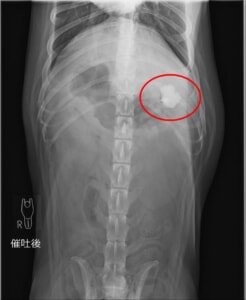

催吐処置をして吐けるだけ吐いてもらいました。

2日後に吐き気があるということで再来院してもらいました。

改めてレントゲン写真を撮ると、吐ききれなかった異物が確認できます。